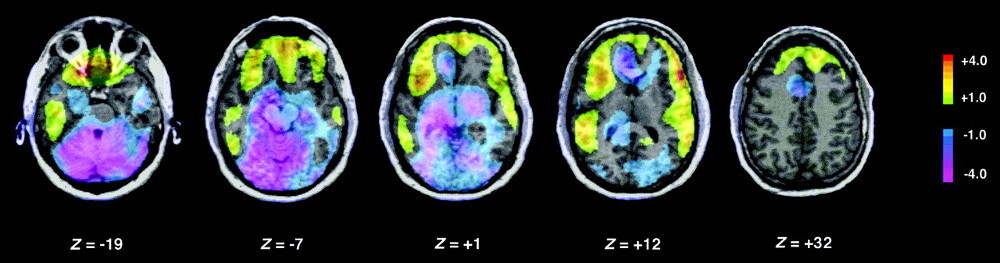

El profesor Antonie Adamantis y su equipo han identificado un “nuevo circuito cerebral en ratones cuya activación causa un rápido despertar e inhibición un sueño profundo”. En los experimentos llevados a cabo, los investigadores han sido capaces de despertar el sueño ligero mediante la estimulación de este mecanismo situado entre el hipocampo y el tálamo.

Mediante la utilización de una serie de técnicas de optogenética, utilizadas habitualmente en investigación neuronal, el equipo de Adamantis han determinado que este circuito cerebral puede marcarse como “objetivo terapéutico de cara a afrontar desórdenes del sueño”.